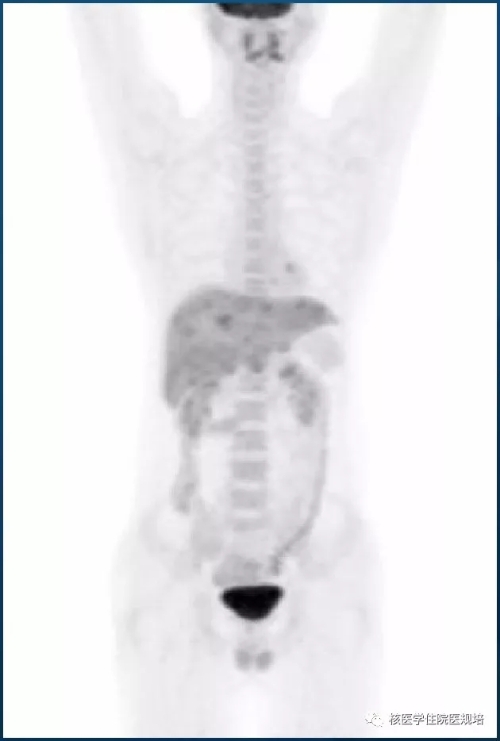

图2. 18F-FDG PET/CT MIP图